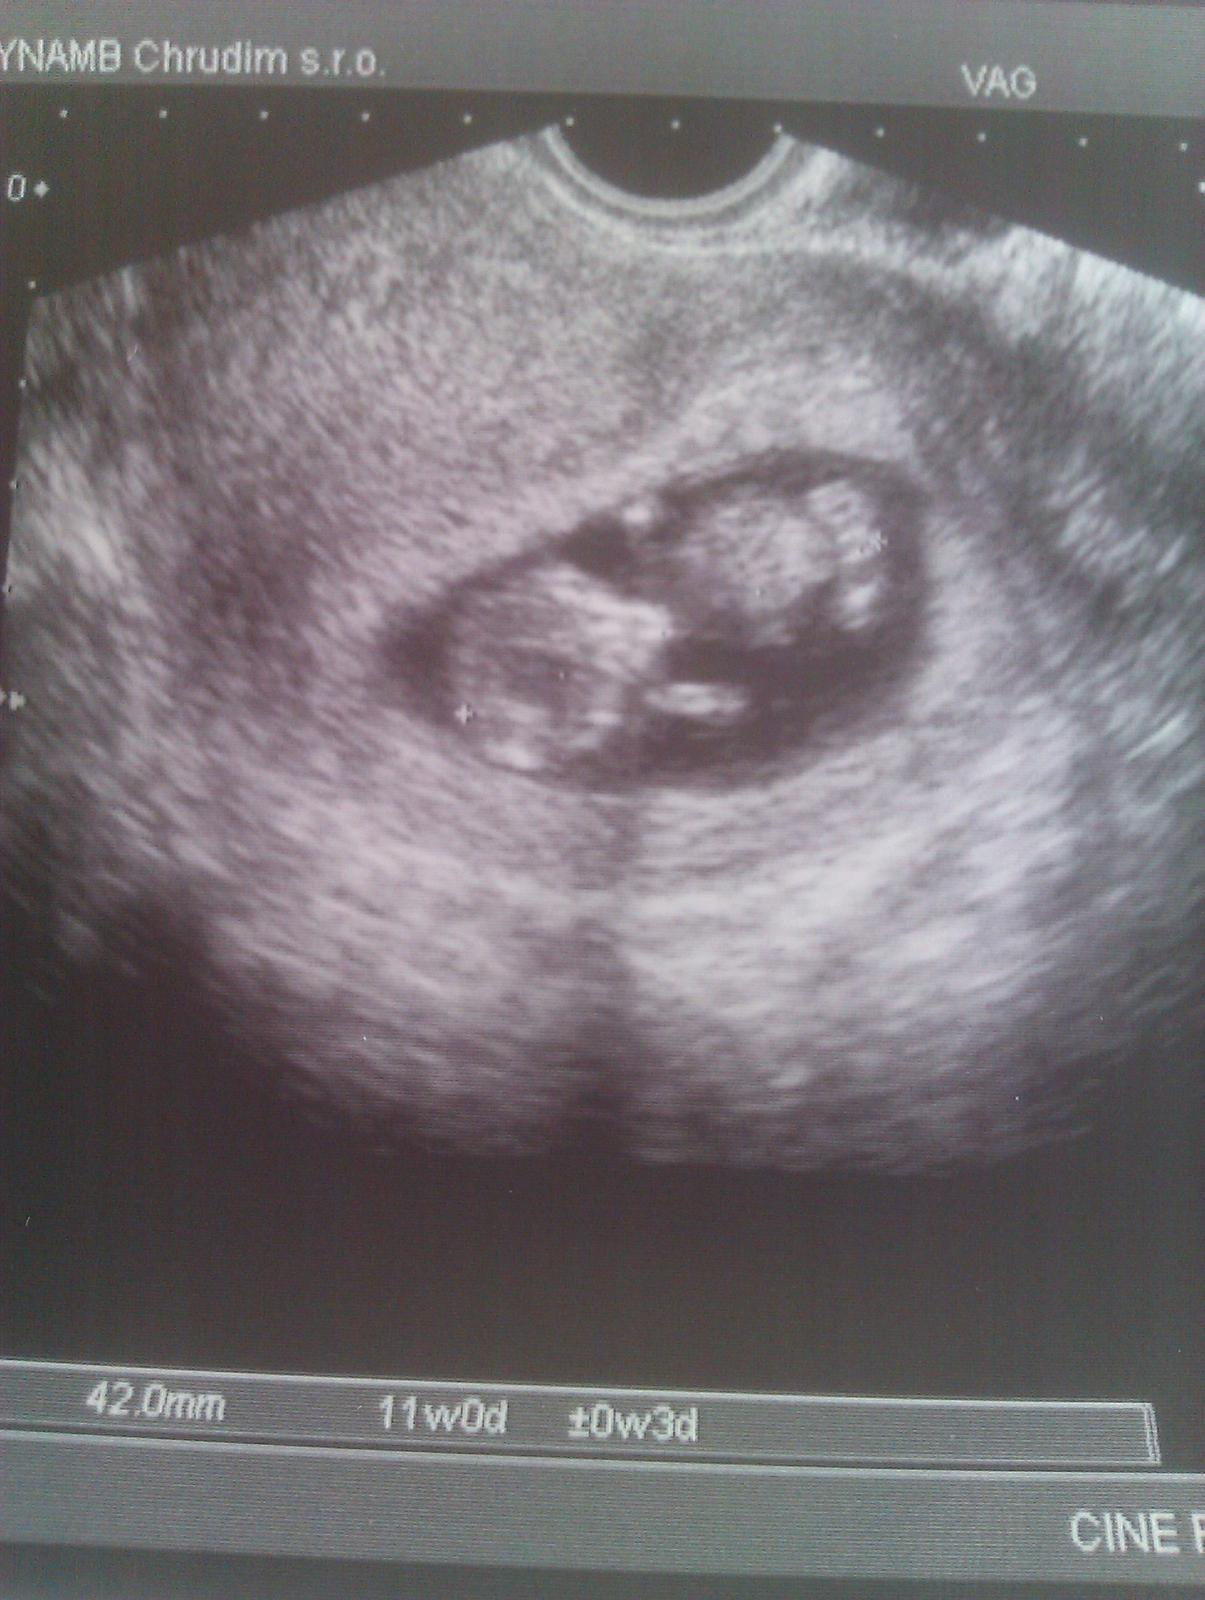

Dnesni prvni poradna,museli jsme Prcinka budit a pak to bylo krasne sledovat jak se hybe,mame 4,5 cm,vse ok,16.7 jedeme na screnning.

Foto dodam z pc,pres tlf mi nejde